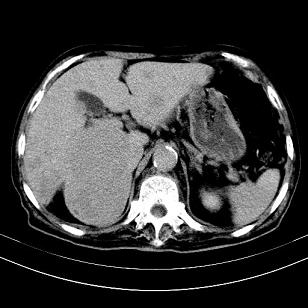

标题: CT19407:肝内还是肝外原发性肿瘤??

男,63岁,高血压病史40余年,

来源-右侧肾上腺。

考虑右侧肾上腺巨大占位;恶性?

肝内多发低密度找;转移瘤?

另:右肾结识,多发小囊肿。

考虑右肝后叶肝癌(部分外生)伴肝内多发性转移;右侧肾上腺区恶性肿瘤并肝转移待排。

考虑右侧肾上腺肿瘤并肝内多发转移。右侧肾上腺呈“八”字形,包括内侧枝及外侧枝,内侧枝受压,考虑外侧枝原发肿瘤。”

考虑肝右后叶肝癌(部分外生)伴肝内多发性转移;不排除右侧肾上腺区恶性嗜铬细胞瘤并肝转移。